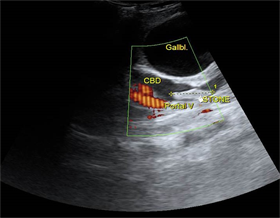

Los hallazgos más significativos de la ecografía abdominal al ingreso fueron (Fig. 1)(Fig.2): Textura hepática homogénea, vesícula dilatada que mide 100x40mm, pared 3,5mm, dilatación de más de 5mm en las vías biliares intrahepáticas con litiasis pequeñas en su interior, colédoco tortuoso, mide 14mm de diámetro con litiasis de 13x7mm en su interior, el resto de las vísceras abdominales sin alteraciones aparentes.

Otras características que pueden detectarse mediante ecografía incluyen cálculos biliares, abscesos hepáticos, "biloma" y colangiocarcinoma. Se puede realizar una aspiración percutánea con aguja fina guiada por ecografía en caso de sospecha de tumor hepático. 11,12 En este caso, la primera investigación por imágenes realizada fue la ecografía de abdomen que muestra un cálculo alargado dentro del colédoco dilatado e imagen ecogénica dentro de las vías biliares intrahepáticas dilatadas y engrosamiento ecogénico adyacente a la pared de la vía biliar. Posteriormente se realizó una tomografía computarizada de abdomen con contraste, para definir la dilatación de la vía biliar que se aprecia mejor en un estudio contrastado, la constitución mixta de las litiasis, propias de los cálculos biliares y sirvió además para descartar otras complicaciones como formación de abscesos, cirrosis hepática, biloma o rotura de la vía biliar con peritonitis y colangiocarcinoma, como vimos la pancreatitis estaba presente como complicación. No se realizó colangiopancreato resonancia a este paciente porque fue remitido a institución terciaria para definir diagnostico y tratamiento, donde fue diagnosticado finalmente con la CPR por los hallazgos de litiasis biliares, estenosis fibrótica y dilatación de las vías biliares.